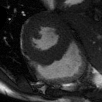

Supervised Deep-Learning (DL)-based reconstruction algorithms have shown state-of-the-art results for highly-undersampled dynamic Magnetic Resonance Imaging (MRI) reconstruction. However, the requirement of excessive high-quality ground-truth data hinders their applications due to the generalization problem. Recently, Implicit Neural Representation (INR) has appeared as a powerful DL-based tool for solving the inverse problem by characterizing the attributes of a signal as a continuous function of corresponding coordinates in an unsupervised manner. In this work, we proposed an INR-based method to improve dynamic MRI reconstruction from highly undersampled k-space data, which only takes spatiotemporal coordinates as inputs. Specifically, the proposed INR represents the dynamic MRI images as an implicit function and encodes them into neural networks. The weights of the network are learned from sparsely-acquired (k, t)-space data itself only, without external training datasets or prior images. Benefiting from the strong implicit continuity regularization of INR together with explicit regularization for low-rankness and sparsity, our proposed method outperforms the compared scan-specific methods at various acceleration factors. E.g., experiments on retrospective cardiac cine datasets show an improvement of 5.5 ~ 7.1 dB in PSNR for extremely high accelerations (up to 41.6-fold). The high-quality and inner continuity of the images provided by INR has great potential to further improve the spatiotemporal resolution of dynamic MRI, without the need of any training data.